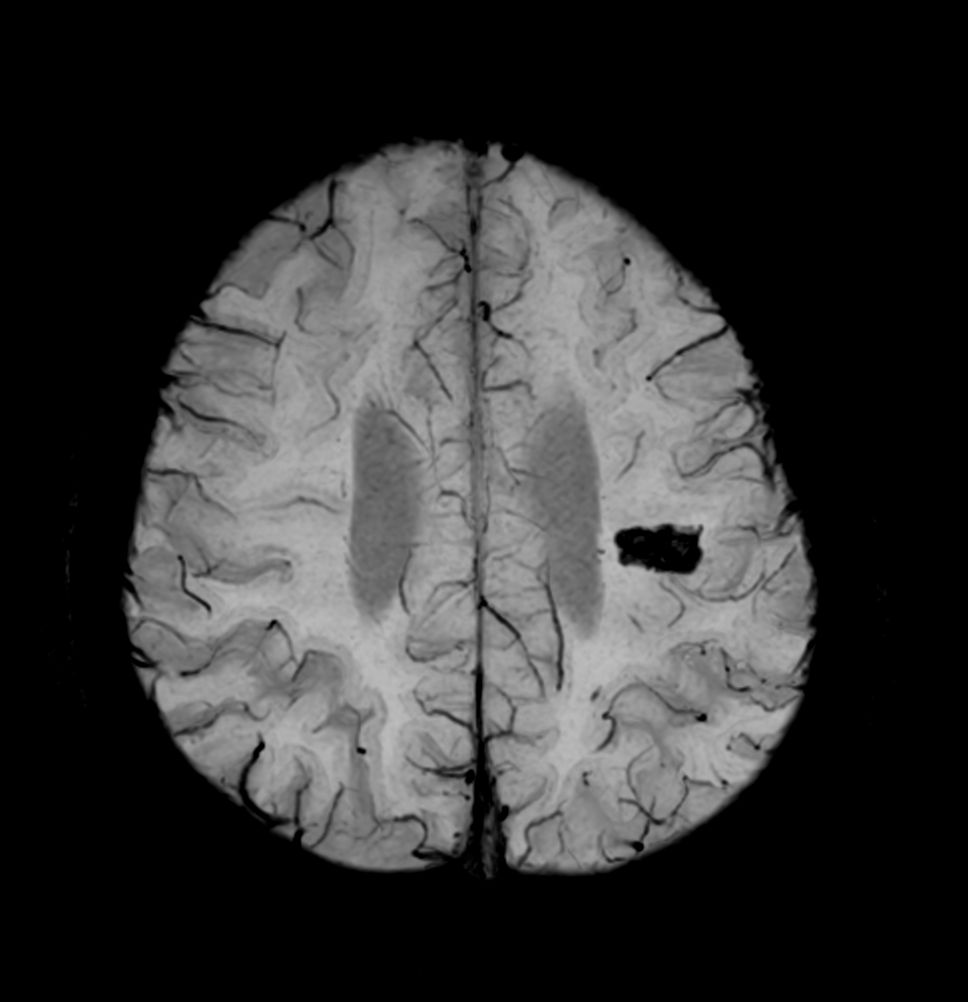

Patient with a small brain infarction. Compressed SENSE acceleration is used to speed up sequences while maintaining equal image quality. Three different diffusion methods are included; A fast 52 secs DWI EPI sequence, a high resolution DWI EPI sequence and a TSE based DWI sequence. A SWIp sequence is included offering high resolution 3D susceptibility weighted imaging to enhance contrast for deoxygenated (venous) blood or calcium deposits. 3D APT sequence is included providing contrast-free brain imaging, addressing the need for more confident diagnosis in brain neuro oncology by using the presence of endogenous cellular proteins to produce an MR signal. And a large FOV TOF MR Angiography sequence is included to check on brain vascular anatomy.

Axial SWIp